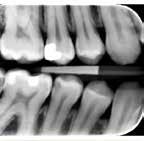

27. LIVSMEDELSVERKET. Hälsosam helhet. (Set 2023 juli). Tilgængelig fra: URL: https://www.livsmedelsverket.se/globalassets/ publikationsdatabas/broschyrer-foldrar/livsmedelsverket_ halsosam-helhet_20160408april-2016.pdf

34. Abreu-Placeres N, Newton JT, Pitts N et al. Understanding dentists’ caries management: The COM-B ICCMS™ questionnaire. Community Dent Oral Epidemiol 2018;46:545-54.